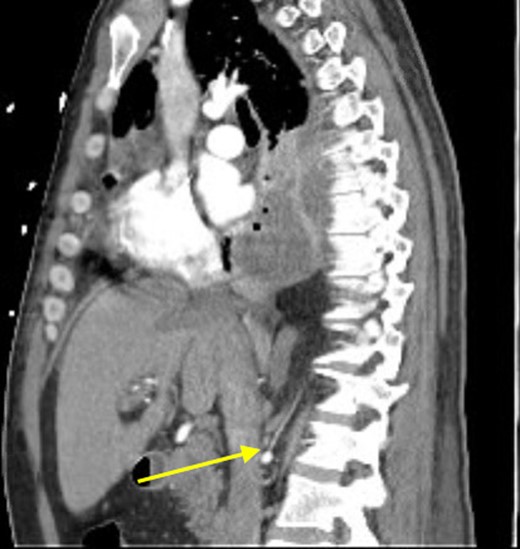

Sagittal view showing anomalous bloody supply originating from proximal right renal artery.

At that time, we started to wonder if this patient had ILPS, which prompted us to scrutinize his prior CT scans. Surprisingly, we noticed an anomalous arterial supply from the right renal artery that traversed through his Bochdalek hernia and into the sequestration (Figs 2 and 3). Two days after the operation, the patient was extubated and his clinical course was relatively benign. Also, no pathogens were detected by microbiological analysis of the intraoperative cultures and bronchial lavage. Pleual biopsies from the first operation just showed some acute fibrinous pleuritis with calcium. One week later, his mental status recovered at baseline, he was breathing without supplemental oxygen and his WBCs count had normalized. The patient was discharged to rehab with follow up in the clinic to discuss surgical resection of the ILPS in order to prevent recurrent symptoms.